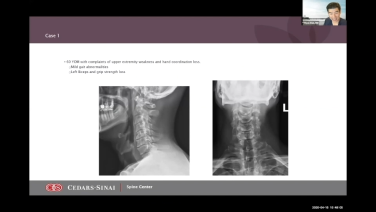

Anterior Cervical Approach & Surgical Pearls with Srinivas Prasad, MD